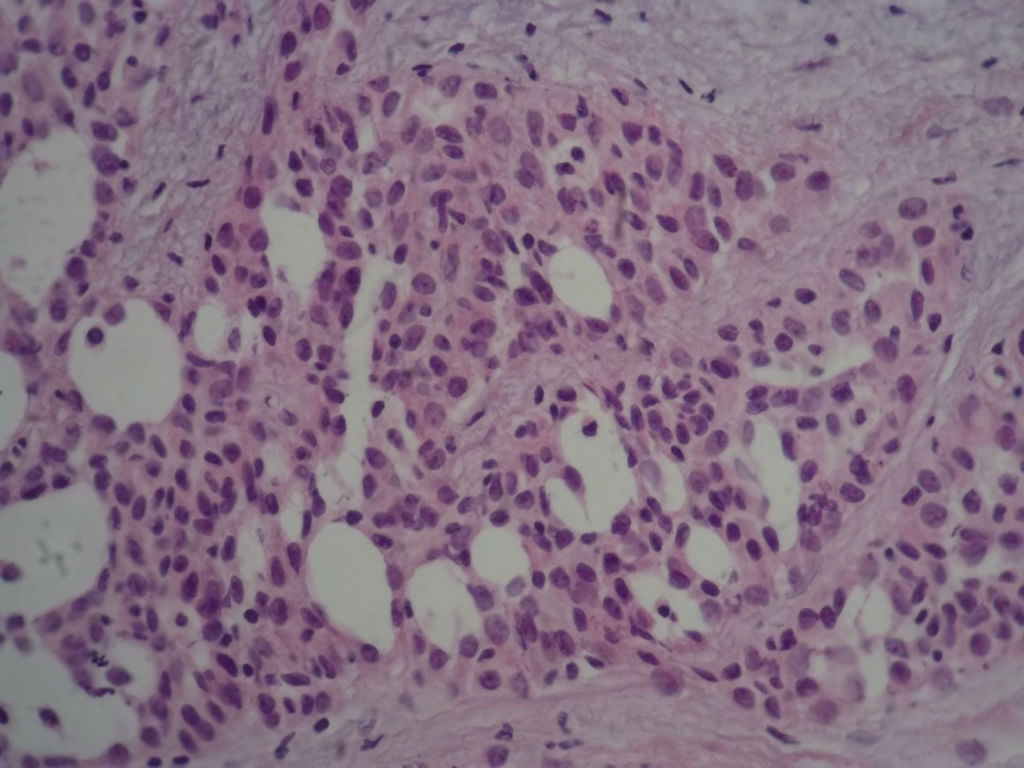

本例太完美了,也非常惊险,真的,至少在我们中国的这个病理环境下能做到这样真心不错。这是个罕见病例,居然冰冻让你碰上了,从冰冻——常规——IHC都完备。我从冰冻看到常规未看免疫组化之前还一直犹豫是不是癌?是癌但一定是您说的分泌性癌吗?看常规时只是觉得浸润性癌够了,后来看到常规的筛状结构+分泌物才确定形态学也够了,就差IHC了,结果您贴出来上级医院的IHC结果真的是3阴,S-100+,高分子量CK部分+,这个表达模式完全符合分泌性癌(我也遇到一个分泌性癌,IHC表达方式完全和您的这例一样),当然必须是结合形态学了。

Secretory breast carcinomas (o0.15% of breast tumors) are associated with a characteristic morphology and a

favorable prognosis. Remarkably, this entity is the only epithelial tumor of the breast with a balanced

determine the phenotypic class (ie luminal A/B, ERBB2, basal-like) of secretory breast carcinoma. A series of six

antibodies. In situ and invasive components shared the same immunoprofile and were ER, PR, ERBB2 negative

with expression of basal cytokeratins. ETV6 gene alterations were present in both in situ and invasive

components, highlighting their genetic similarities. The immunoprofile data (triple-negative with expression of

basal markers) showed that secretory breast carcinomas with ETV6-NTRK3 fusion gene belong to the

phenotypic basal-like spectrum of breast carcinomas. These results support the hypothesis that secretory

breast carcinomas have immunohistochemical and genetic features that distinguish them from other basal-like

tumors of the breast.